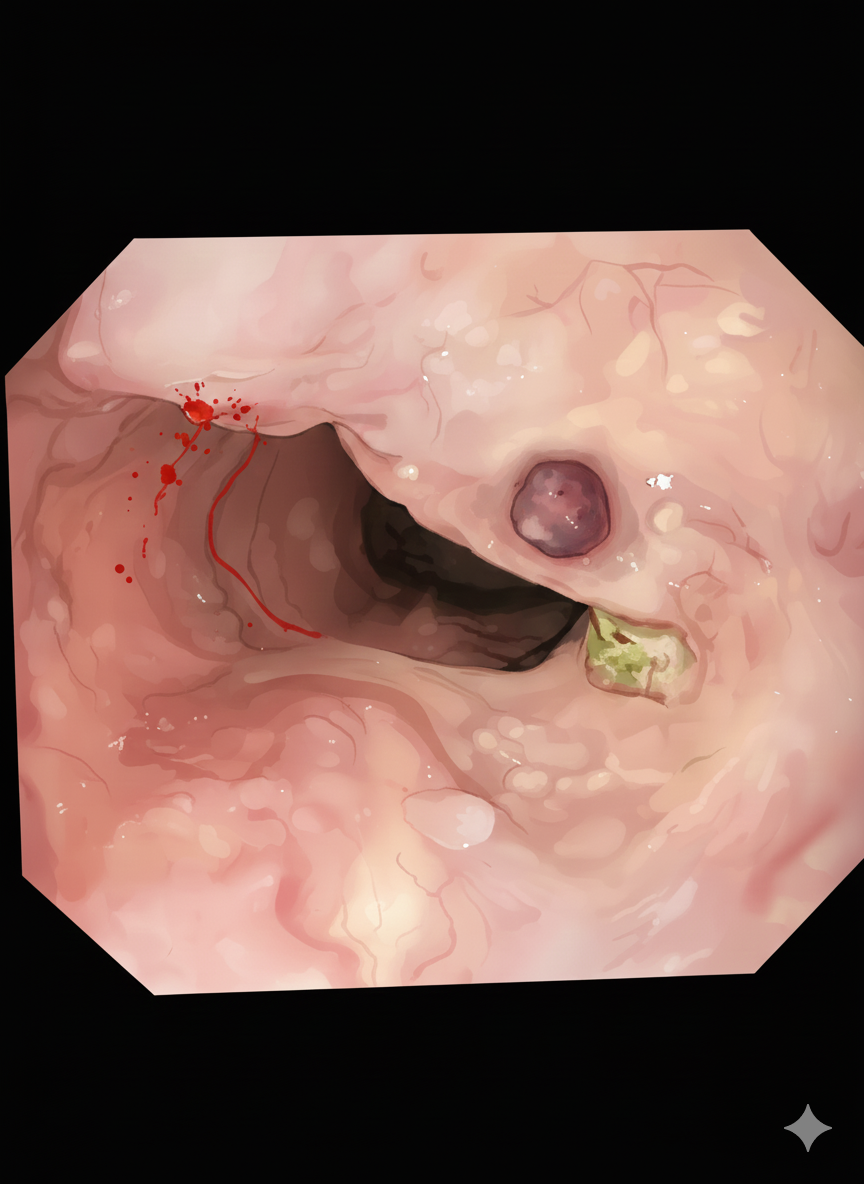

이전에 ligation을 두 차례 시행했고 시행한 자리 주변에서 출혈을 했다가 멎은 흔적이 있었다. post banding ulcer가 주변 혈관을 자극해서 출혈이 생긴 것 같았다. 문제는 다시 ligation을 해도 그곳을 잡기는 어려울 테고 그와 인접한 Collateral vessel에서도 출혈을 했다가 멈춘 흔적이 보였다. 이래나 저래나 시술을 하면 출혈이 예견된 상황이었다.

SB tube를 사용해 본 적이 없다는 간호사와 함께 EVL 준비를 했다. 내시경실에서는 일 년에 많아 봤자 SB-tube사용은 세네 번이 전부이다. 몇 년간 내시경 간호사 일을 해도 사용해 본 적이 없는 간호사도 많았다. ligation을 하면 혈관을 당겨서 묶는데, 당기는 중에 출혈이 생기기도 한다. 이번의 경우는 이전에 시행한 banding ulcer scar가 주변의 병변이 딸려오지 않게 해서 시술이 쉽게 진행되진 않았다. 몇 번의 시도 끝에 출혈부위를 묶을 수 있었다. 이 정도는 예측 가능한 범위였기에 놀라지 않았지만, 담당 간호사는 당황한 것처럼 보였다. 혈관이 크게 찢어지지 않아서 출혈을 잡을 수 있었다. varix bleeding은 출혈량이 많고 내시경 상에서는 큰 화면에서 출혈이 보이기 때문에 시각적인 공포가 있었다.

실사를 바탕으로 구글 AI로 만든 이미지